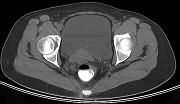

问题 男,67岁,排便习惯改变,血便三个月入院,CT检查如图所示,下列说法错误的是 ( )

选项 A.直肠肠腔局限性增厚 B.其表面欠光整,边界欠清晰 C.可做直肠指检及活检以确定病变性质 D.此为直肠息肉 E.此为直肠癌

答案 D